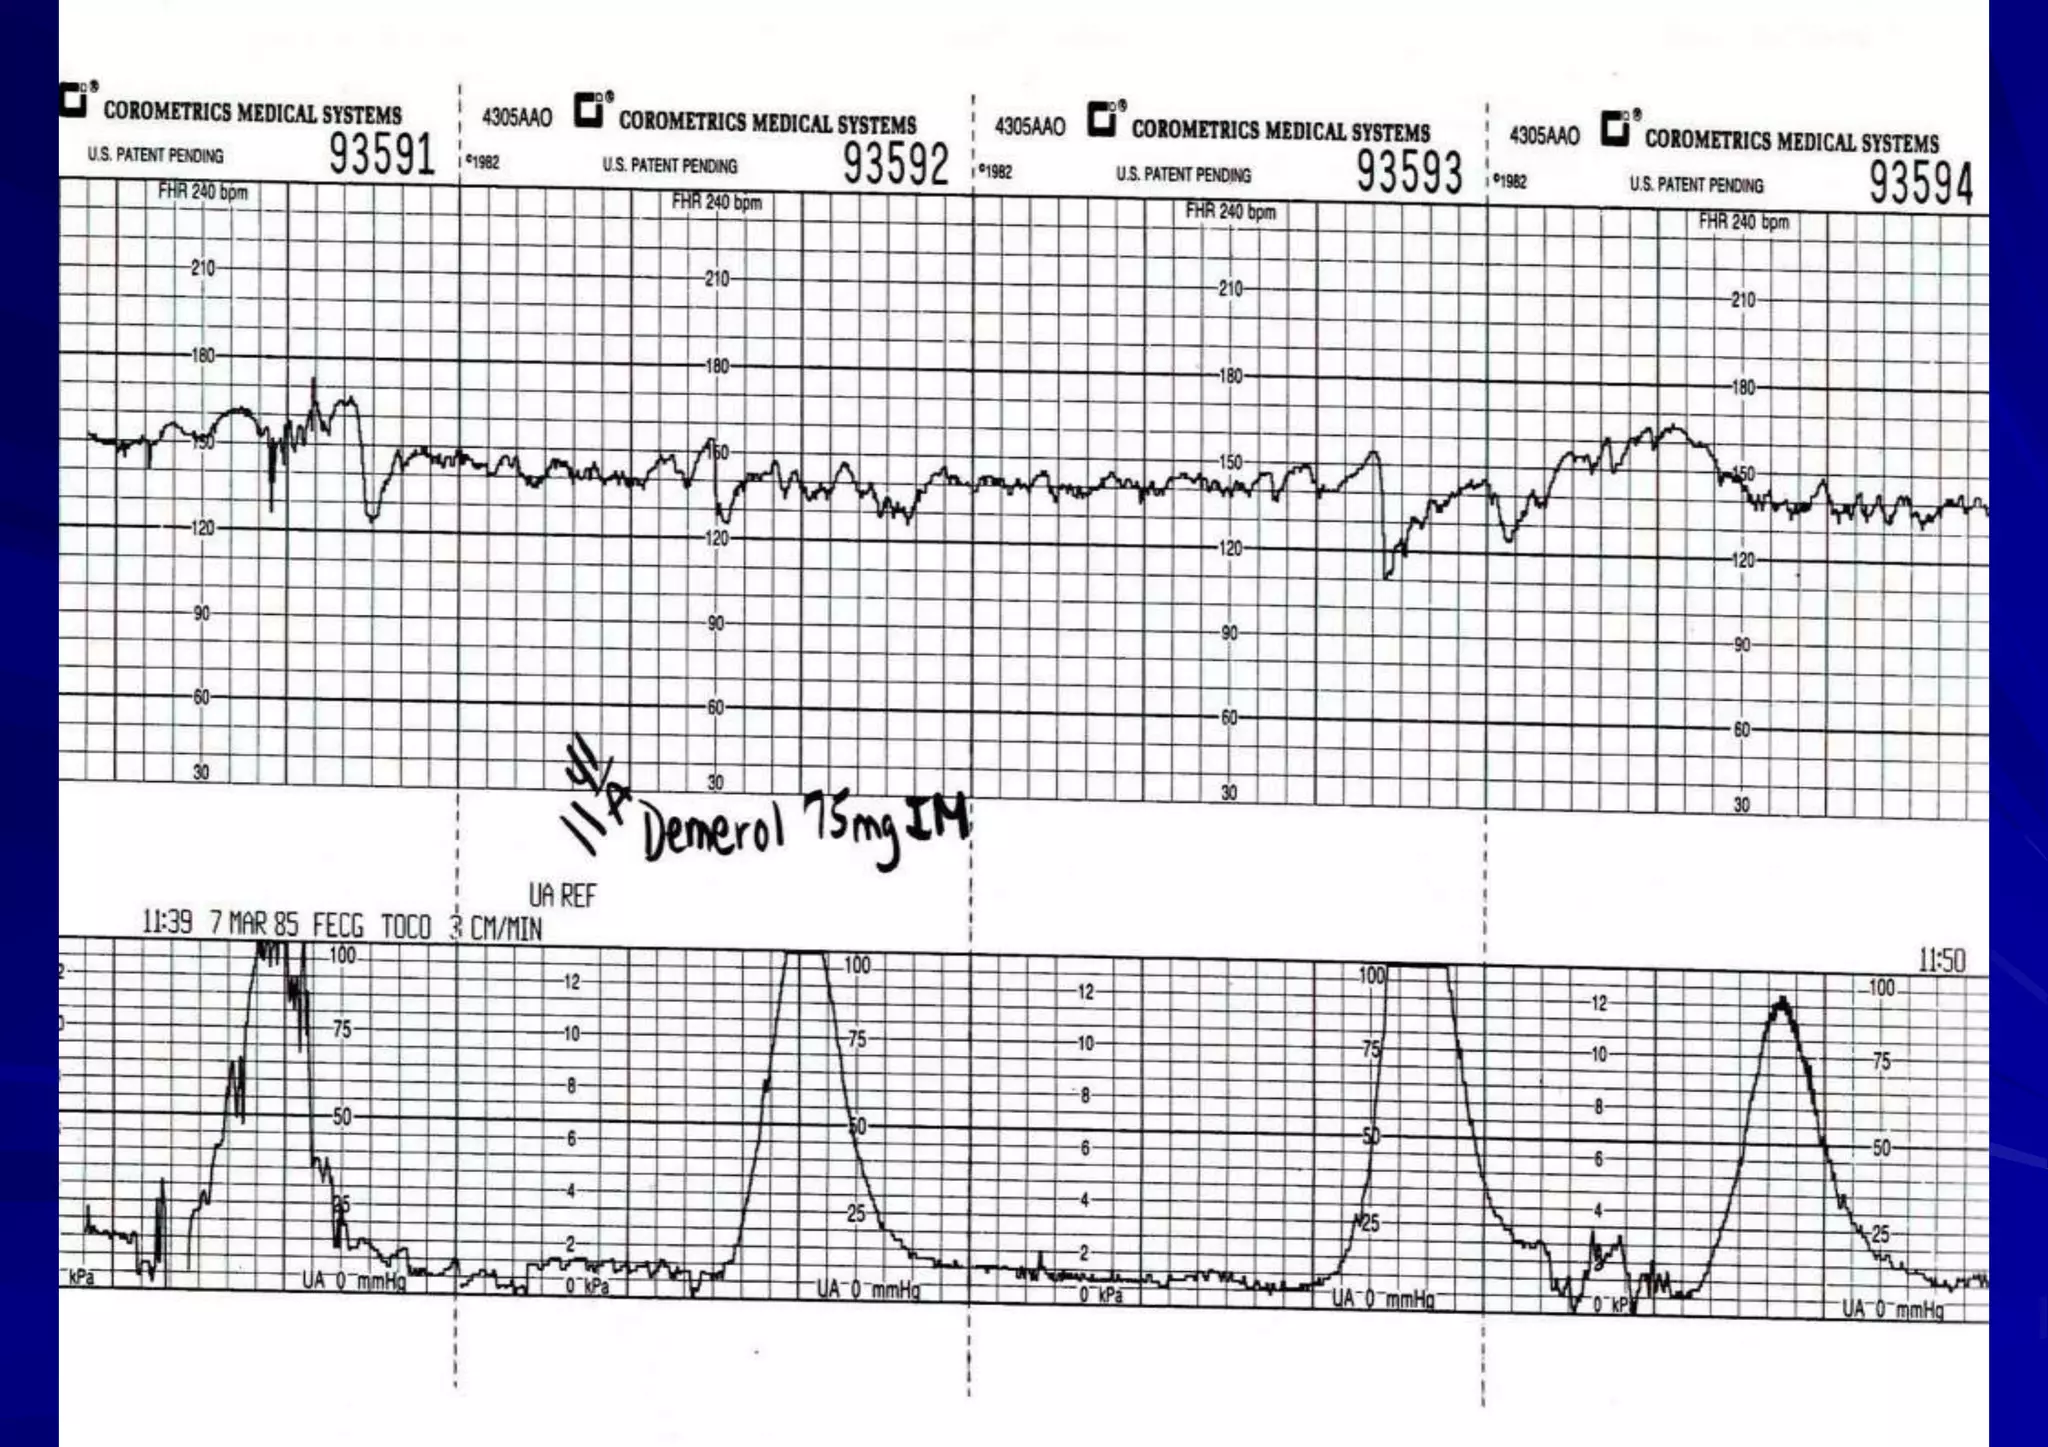

Causes of decreased baseline variability

• Fetal sleeping period.

• Drugs:-( narcotics ,tranquilizers ,MgSO4 )

• Fetal compromise (with decelerations)

• Extremely preterm fetus,

• Fetal cardiac anomaly,

• Preexisting fetal neurologic injury